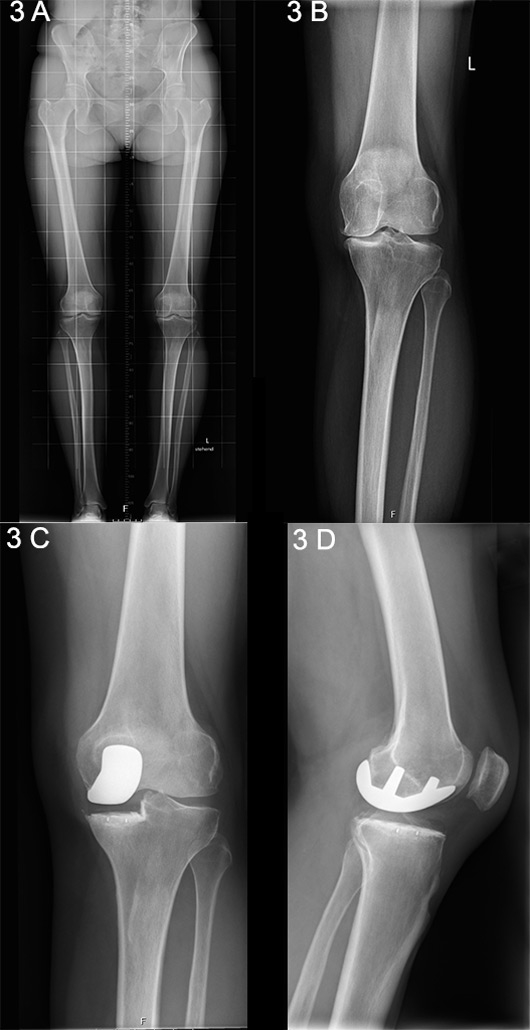

Figure 3

A. Long-standing X-ray showing unicompartmental medial knee osteoarthritis. B. Anteroposterior X-ray showing unicompartmental medial knee osteoarthritis. C. Postoperative anteroposterior X-ray following unicondylar knee arthroplasty (UKA). D. Lateral X-ray following UKA.

Unicompartmental arthroplasty

Unicompartmental, or unicondylar, knee arthroplasty (UKA) is the preferred choice when the intention is to preserve the intrinsic joint stabilising structures, as well as healthy joint compartments [23] (fig. 3 A‒D) [24]. The general indication for consideration of a UKA procedure is based an isolated involvement of either the lateral or medial tibiofemoral compartment, identified upon clinical and radiographic examination [25, 26]. Silent preoperative radiographic signs of patellofemoral joint disease can be ignored and are not considered a contraindication for UKA [27, 28]. There is only evidence to suggest that, despite a good outcome, patients with lateral patellofemoral OA receiving medial UKA have slightly inferior results than those without, as has been reported by the Oxford Group [29].

An intact anterior cruciate ligament (ACL) is an important prerequisite for UKA, as the altered knee kinematics and contact stresses would otherwise increase failure rates [30]. There are concerns over an increased failure rate with UKA versus TKA due to aseptic loosening and the progression of arthritis in the contralateral compartment [25]. Technique-associated factors, mainly the achievement of correct alignment during surgery, have been proven predictive for increased polyethylene wear and contralateral progression of OA due to undesirable peak loads [31, 32]. If correctly indicated and performed, UKA can provide long-lasting successful results [33, 34].